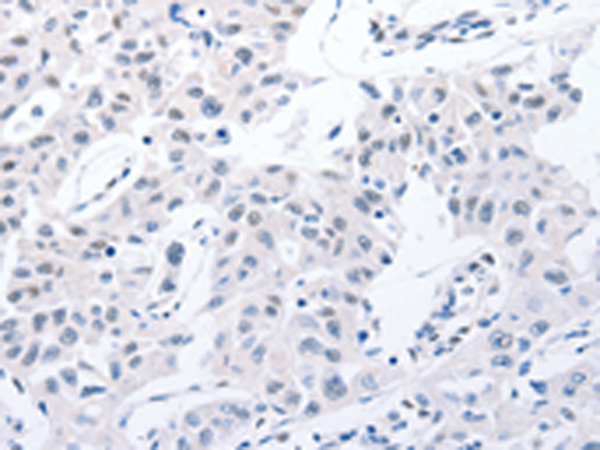

分类: 科研抗体货号: P11039别名: MMP-27应用: IHC反应种属: Human